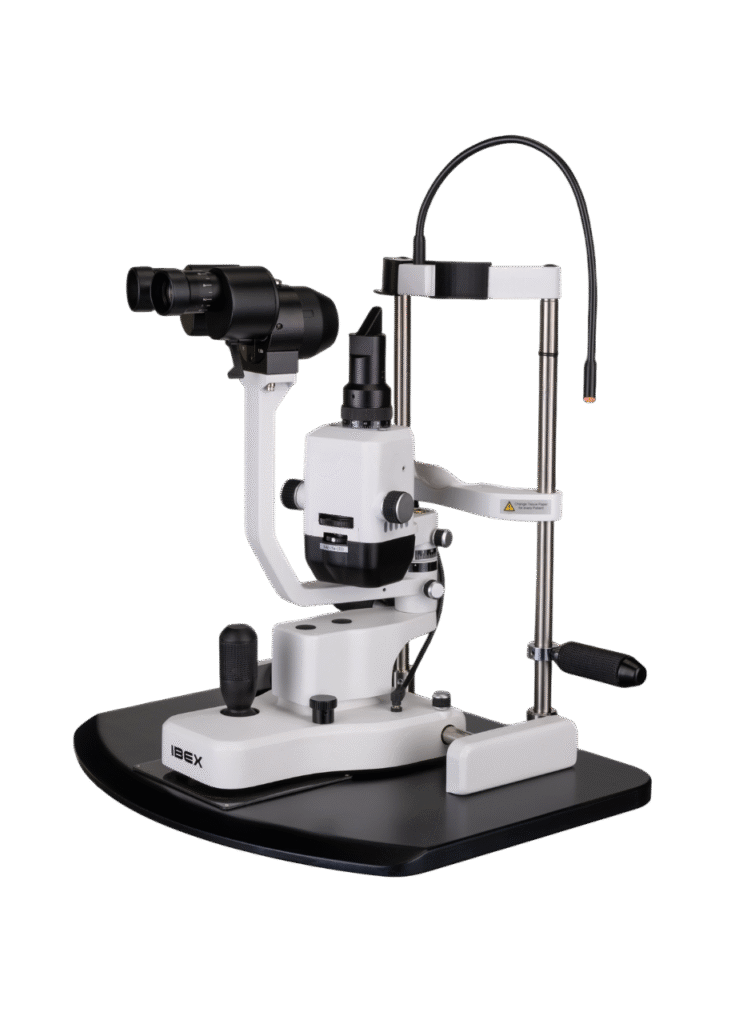

Opteon™ Slit Lamp Imaging + Meibography

Opteon was born and developed in the clinic, meticulously tested, and perfected through countless hours to ensure that it flows with your exam routine — delivering unmatched reliability and efficiency.